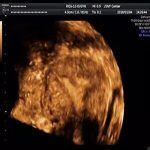

宫腔粘连检查动态数字化子宫输卵管造影 2020/04/10 分类:宫腔粘连 1208 0动态数字化宫腔子宫输卵管造影(HSG)能明确宫腔粘连,但是无法显示子宫内膜纤维化及稀疏的粘连带。 标签:宫腔粘连检查 上一篇: 宫腔粘连病因多与刮宫有关系 下一篇: 宫腔粘连全景彩超检查